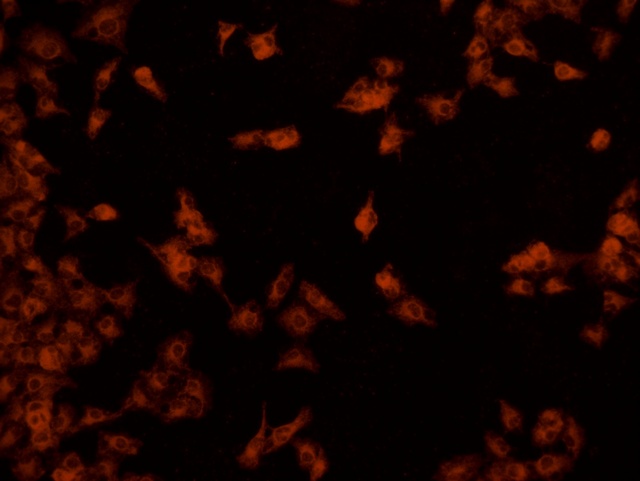

南華大學(xué)在生物醫(yī)學(xué)研究領(lǐng)域一直走在學(xué)術(shù)前沿,近日,該校引進(jìn)Mshot明美的倒置熒光顯微鏡MF52-N,搭配顯微鏡相機(jī)MSX2,為細(xì)胞切片標(biāo)本的研究提供了強(qiáng)大的技術(shù)支持,進(jìn)一步提升了科研實(shí)力。

MF52-N倒置熒光顯微鏡以其數(shù)顯LED熒光模塊和深度優(yōu)化的光路設(shè)計(jì),成為細(xì)胞切片觀察的理想選擇。其簡(jiǎn)單易用的熒光激發(fā)操作,大大降低了實(shí)驗(yàn)難度,提升了工作效率。同時(shí),該顯微鏡還能提供高質(zhì)量的相襯、熒光和明場(chǎng)成像,確??蒲腥藛T能夠捕捉到細(xì)胞切片的每一個(gè)細(xì)節(jié)。

在南華大學(xué)的實(shí)驗(yàn)室中,科研人員正借助這套先進(jìn)的顯微系統(tǒng),對(duì)細(xì)胞切片標(biāo)本進(jìn)行深入探索。

此外,MSX2顯微鏡相機(jī)的加入,更是如虎添翼。這款相機(jī)以其高分辨率和敏銳的圖像捕捉能力,記錄了實(shí)驗(yàn)過程中的每一個(gè)重要瞬間,為數(shù)據(jù)分析與論文發(fā)表提供了有力支持。